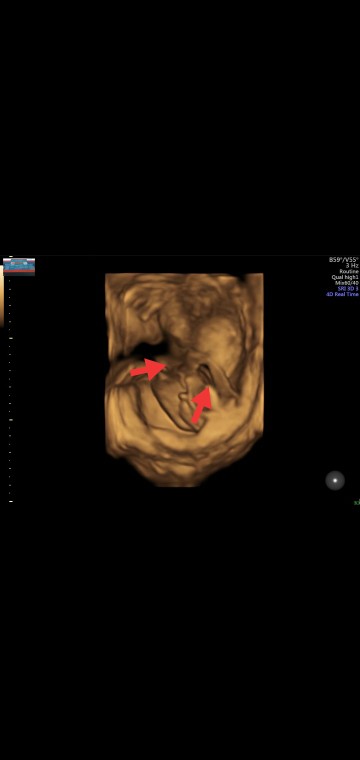

foto hasil usg4d

Emang iya bun itu kata dokternya perempuan, tapi pas ter akhir usg4dnya ...,kata dokternya" ko ada gununganya,tapi ga keliatan monasnya,ini kaya mis v nya ada"gitu kata dokternya ,jadi nyimpulinnya cowok dulu bun,karna ada gununganya,aku juga jadi bingung bun,mungkin ada bunda2 yg lebih paham dari foto ini.....??